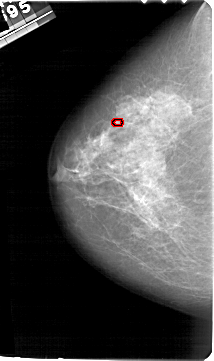

FILE: A_1631_1.LEFT_CC.OVERLAY

TOTAL_ABNORMALITIES 1

ABNORMALITY 1

LESION_TYPE CALCIFICATION TYPE PLEOMORPHIC DISTRIBUTION CLUSTERED

ASSESSMENT 4

SUBTLETY 2

PATHOLOGY BENIGN

TOTAL_OUTLINES 1

BOUNDARY